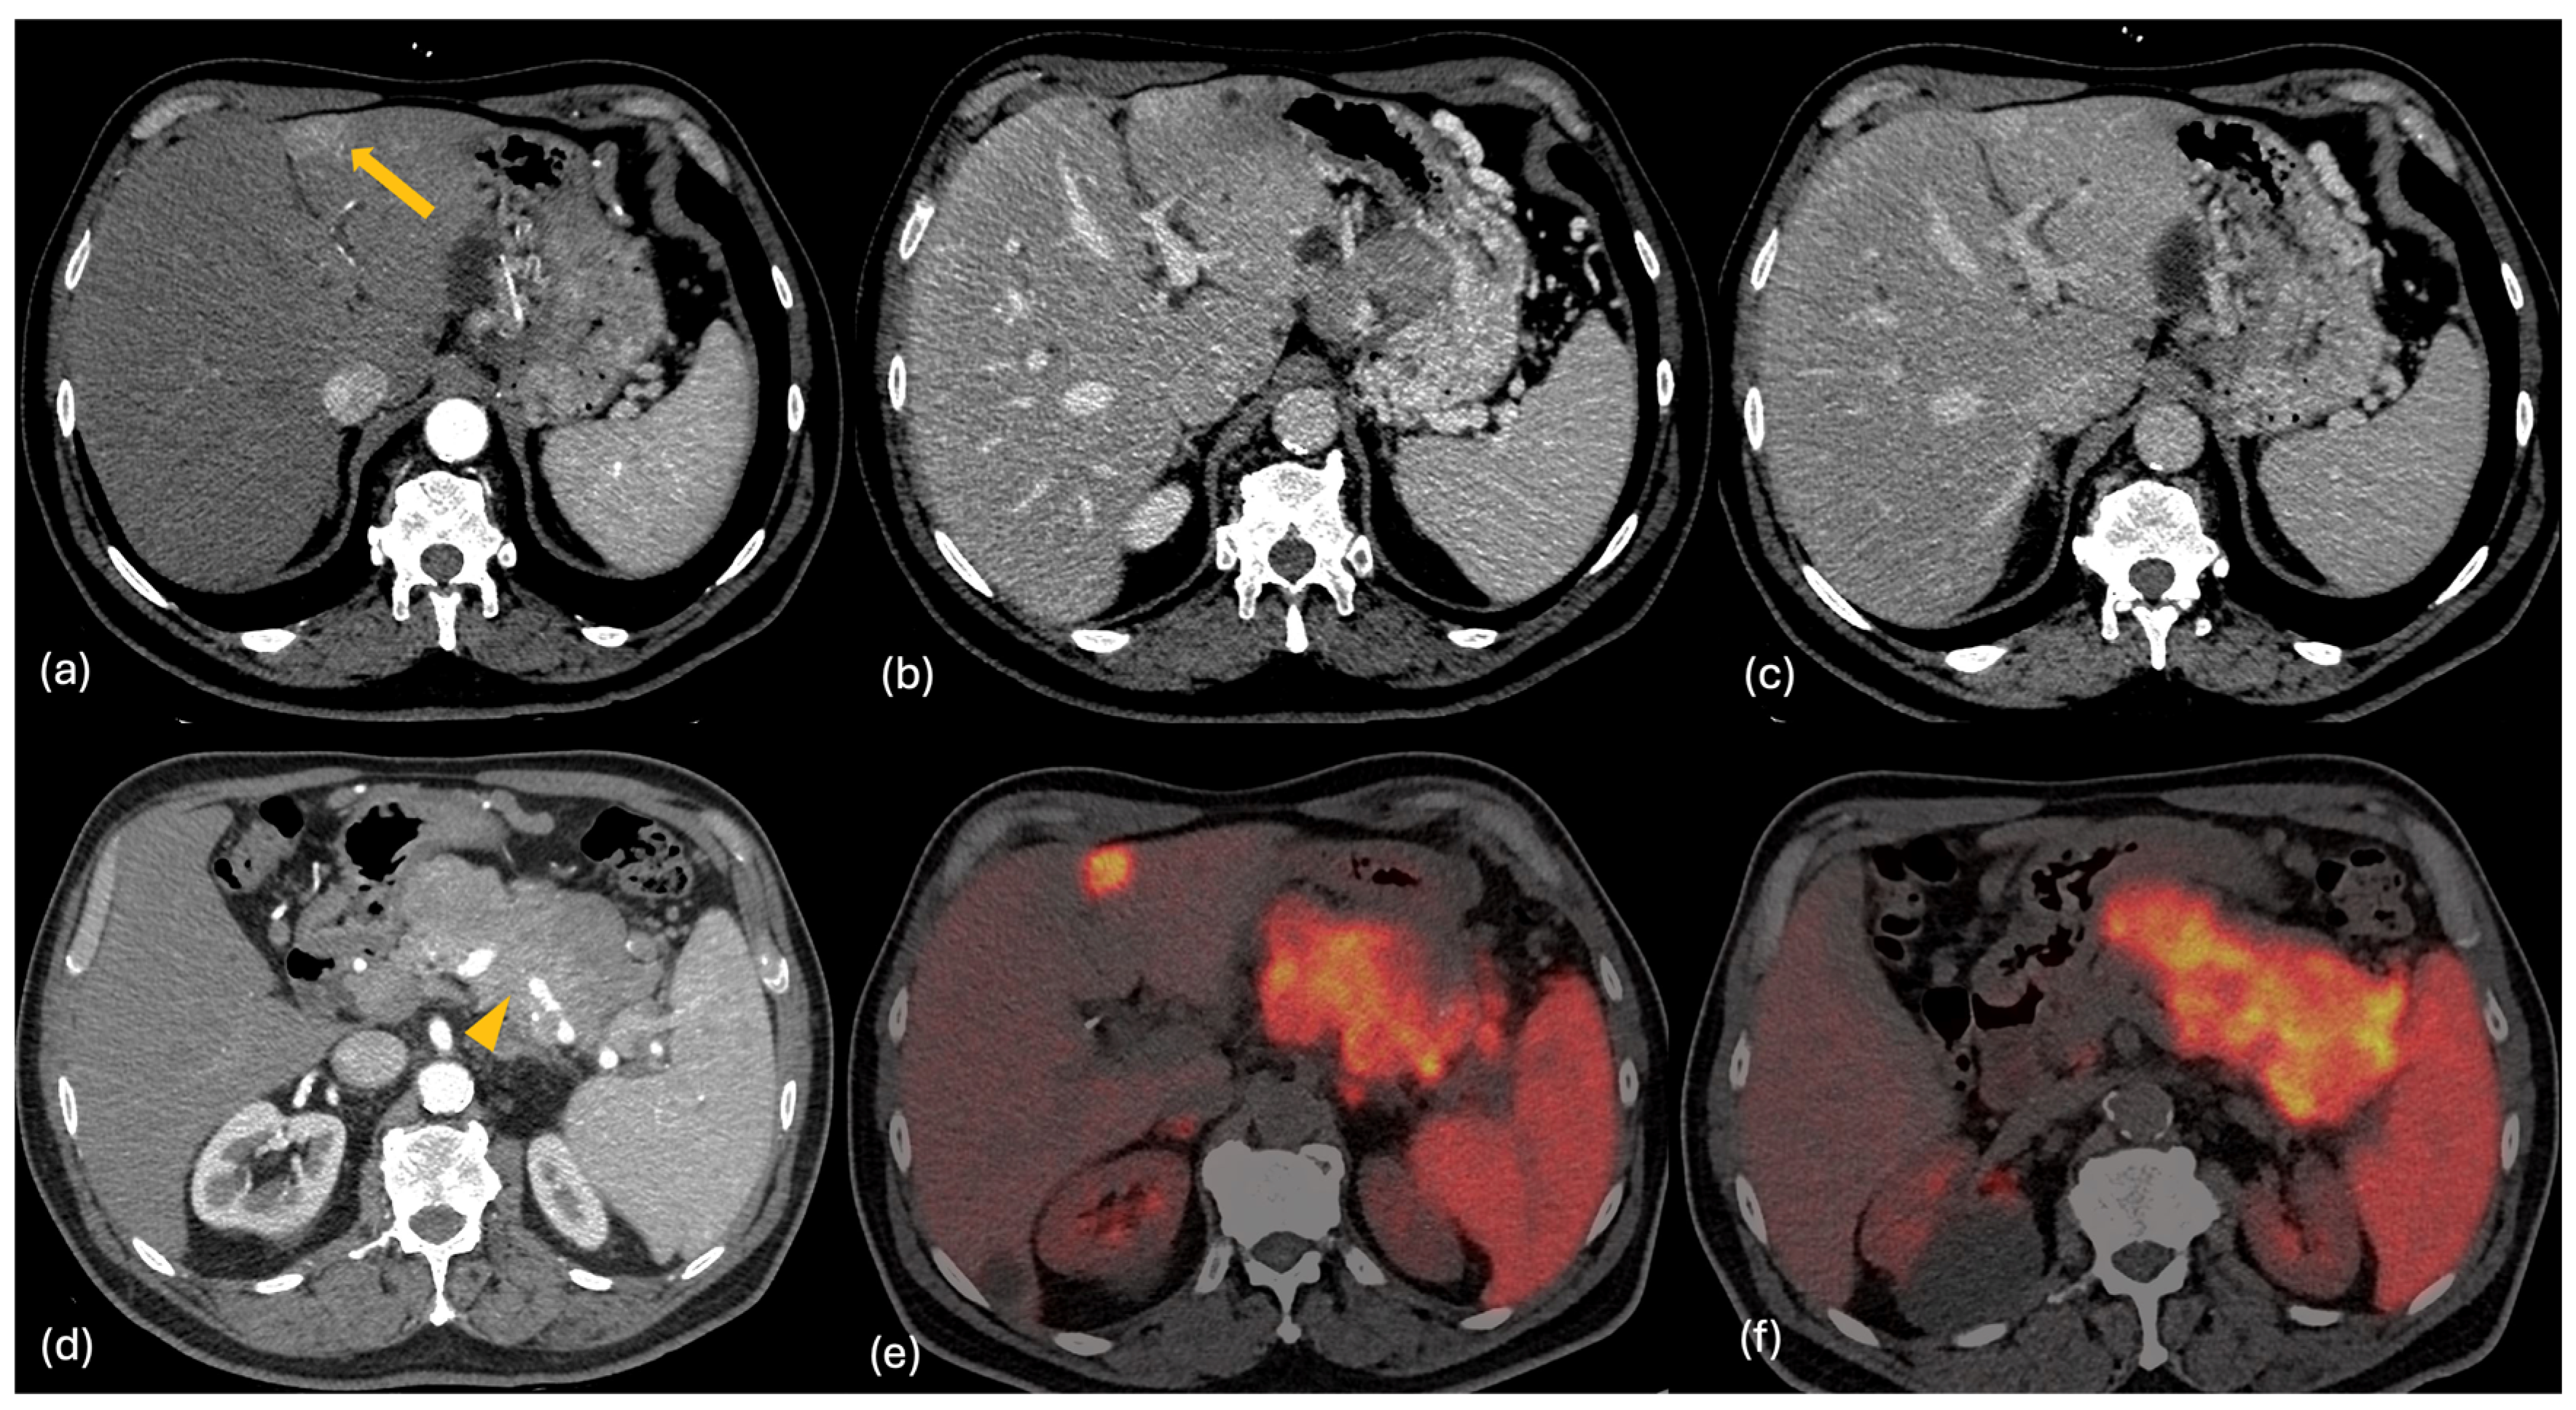

2.2. CT

- Gulpinar, B.; Peker, E.; Kul, M.; Elhan, A.H.; Haliloglu, N. Liver metastases of neuroendocrine tumors: Is it possible to diagnose different histologic subtypes depending on multiphasic CT features? Abdom. Radiol. 2019, 44, 2147–2155. [Google Scholar] [CrossRef] [PubMed]

- Ronot, M.; Cuccioli, F.; Dioguardi Burgio, M.; Vullierme, M.P.; Hentic, O.; Ruszniewski, P.; d’Assignies, G.; Vilgrain, V. Neuroendocrine liver metastases: Vascular patterns on triple-phase MDCT are indicative of primary tumour location. Eur. J. Radiol. 2017, 89, 156–162. [Google Scholar] [CrossRef] [PubMed]

- Foley, W.D.; Mallisee, T.A.; Hohenwalter, M.D.; Wilson, C.R.; Quiroz, F.A.; Taylor, A.J. Multiphase hepatic CT with a multirow detector CT scanner. AJR Am. J. Roentgenol. 2000, 175, 679–685. [Google Scholar] [CrossRef] [PubMed]

- Ronot, M.; Clift, A.K.; Baum, R.P.; Singh, A.; Kulkarni, H.R.; Frilling, A.; Vilgrain, V. Morphological and Functional Imaging for Detecting and Assessing the Resectability of Neuroendocrine Liver Metastases. Neuroendocrinology 2018, 106, 74–88. [Google Scholar] [CrossRef] [PubMed]

- Grazzini, G.; Danti, G.; Cozzi, D.; Lanzetta, M.M.; Addeo, G.; Falchini, M.; Masserelli, A.; Pradella, S.; Miele, V. Diagnostic imaging of gastrointestinal neuroendocrine tumours (GI-NETs): Relationship between MDCT features and 2010 WHO classification. Radiol. Med. 2019, 124, 94–102. [Google Scholar] [CrossRef] [PubMed]

2.4. PET-CT

- Poeppel, T.D.; Binse, I.; Petersenn, S.; Lahner, H.; Schott, M.; Antoch, G.; Brandau, W.; Bockisch, A.; Boy, C. 68Ga-DOTATOC versus 68Ga-DOTATATE PET/CT in functional imaging of neuroendocrine tumors. J. Nucl. Med. 2011, 52, 1864–1870. [Google Scholar] [CrossRef] [PubMed]

- Haug, A.R.; Auernhammer, C.J.; Wängler, B.; Schmidt, G.P.; Uebleis, C.; Göke, B.; Cumming, P.; Bartenstein, P.; Tiling, R.; Hacker, M. 68Ga-DOTATATE PET/CT for the early prediction of response to somatostatin receptor-mediated radionuclide therapy in patients with well-differentiated neuroendocrine tumors. J. Nucl. Med. 2010, 51, 1349–1356. [Google Scholar] [CrossRef] [PubMed]

- Sanli, Y.; Garg, I.; Kandathil, A.; Kendi, T.; Zanetti, M.J.B.; Kuyumcu, S.; Subramaniam, R.M. Neuroendocrine Tumor Diagnosis and Management: 68Ga-DOTATATE PET/CT. AJR Am. J. Roentgenol. 2018, 211, 267–277. [Google Scholar] [CrossRef] [PubMed]

- Fabritius, M.P.; Soltani, V.; Cyran, C.C.; Ricke, J.; Bartenstein, P.; Auernhammer, C.J.; Spitzweg, C.; Schnitzer, M.L.; Ebner, R.; Mansournia, S.; et al. Diagnostic accuracy of SSR-PET/CT compared to histopathology in the identification of liver metastases from well-differentiated neuroendocrine tumors. Cancer Imaging 2023, 23, 92. [Google Scholar] [CrossRef] [PubMed]